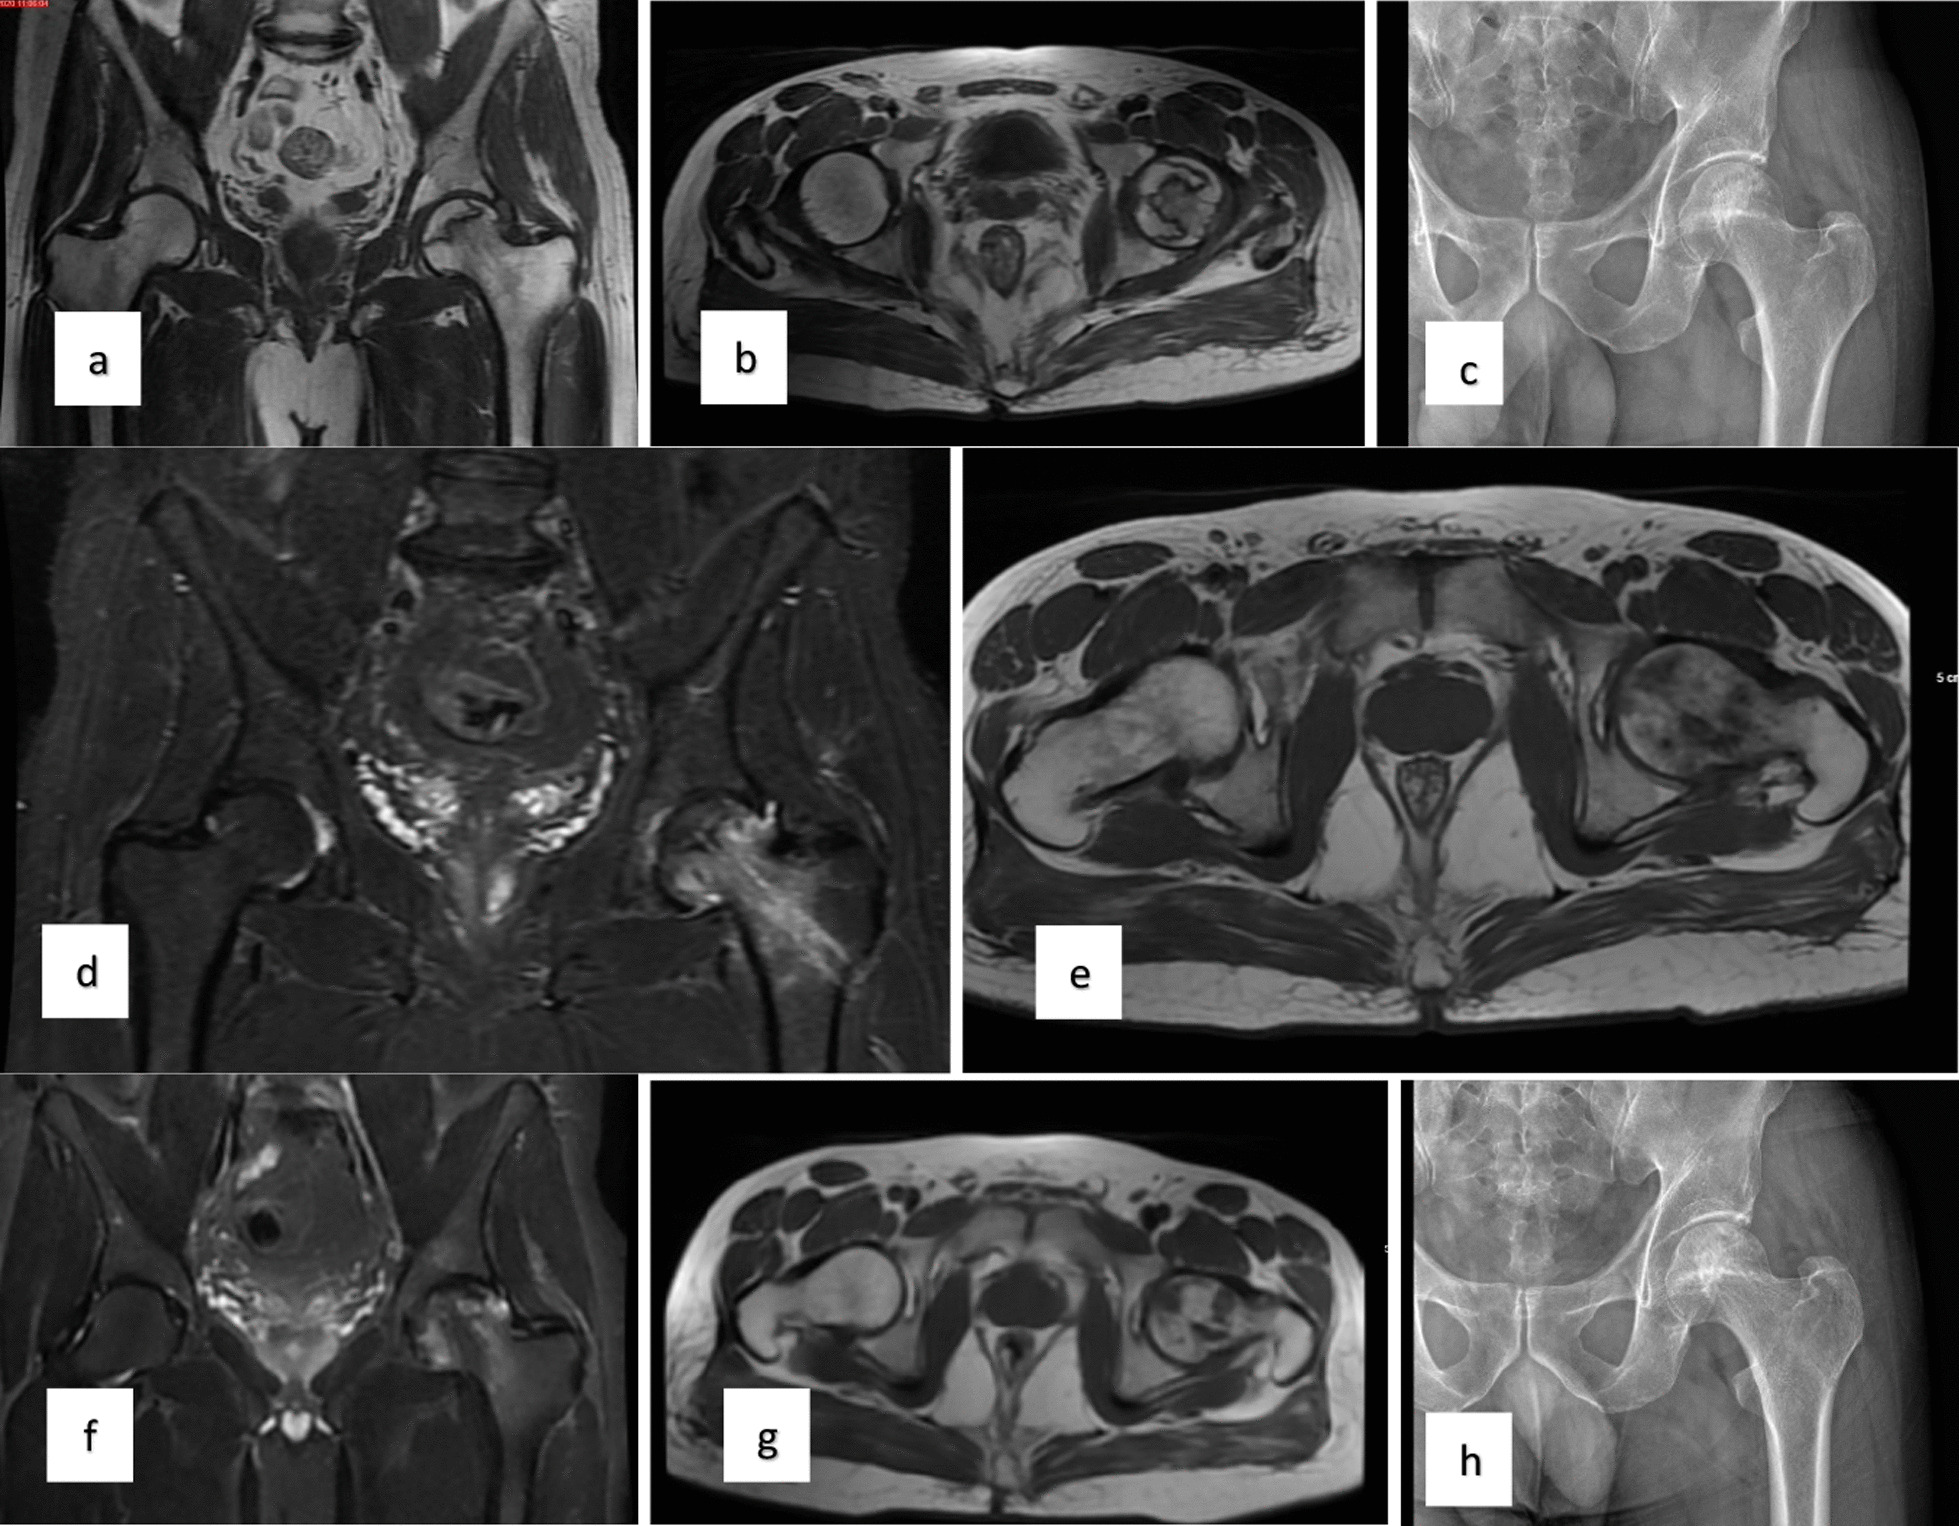

對患者的術前、3個月、6個月、1年和2年隨訪進行評估(圖1)。

圖1:a–c左股骨頭缺血性壞死患者的術前MR和X射線圖像,d-e術后3個月的MR,f–h : 術后第二年的MR和X射線圖像